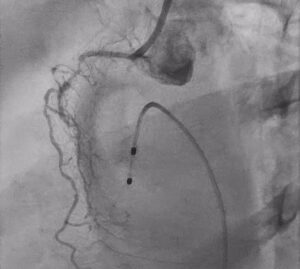

Rotational Atherectomy as a Lesion-Modification Strategy

After exchanging to a dedicated rota wire, the next step was rotational atherectomy, performed in a segmental manner from the proximal RCA up to the crux.

This was the key turning point in the case.

In diffuse calcified disease, especially in CTO segments, adequate lesion preparation is what determines whether the rest of the PCI will be smooth or compromised. Without sufficient calcium modification, balloon expansion remains poor, device delivery is difficult, and final stent expansion may be suboptimal.

The aim of atherectomy here was not simply to “debulk,” but to create a more modifiable pathway through a long, resistant, heavily calcified vessel. In lesions like this, atherectomy plays a crucial role in transforming an undilatable artery into one that can be prepared properly for definitive PCI.

Additional Plaque Preparation Before Stenting

After atherectomy, the vessel was further modified using an Apertha scoring balloon.

This was an important adjunctive step. In calcified coronary intervention, success often comes from combining techniques rather than relying on a single modality. Atherectomy helps create initial plaque modification, but scoring balloons can further improve lesion compliance, especially when calcium has mixed or irregular morphology.

This combined preparation allowed the lesion to become more receptive to stent delivery and expansion.

The procedure then progressed to long-segment stenting from proximal to distal RCA, with guide extension catheter support to facilitate equipment delivery across the treated vessel.

In long, calcified, complex RCA interventions, guide support often becomes a major determinant of success. Adequate support reduces friction, improves deliverability, and helps complete the procedure more efficiently in anatomy that would otherwise resist device passage.